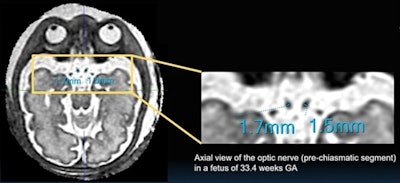

Additionally, among the 3D slice-to-volume cases, prechiasmatic optic nerve width was successfully measured bilaterally in 53 cases, optic chiasm width in all cases, and bilateral optic tract width in 30 cases.

The team also used a linear regression fit to estimate the relationship between optic chiasm (OCW) width in millimeters in normal fetuses and gestational age (GA) in weeks. It came up with the equation of OCW = 0.11 × GA + 2.0 (R^2 = 0.30). In other words, about 30% of optic chiasm and nerve width can be attributed to gestational age. Similarly, the relationship between prechiasmatic (PC) optic nerve width and GA was estimated as PC = 0.04 × GA + 0.24 (R^2 = 0.34).